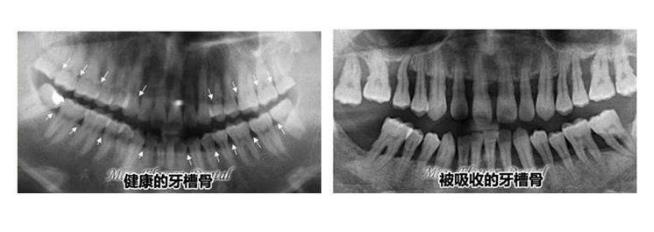

3、廢用性:用進廢退,這是很多人都明白的道理,一般老年人沒有了牙齒後,牙齦和牙槽骨沒有足夠的刺激,就會(hui) 導致牙齦萎縮,牙槽骨吸收的情況。因此,建議牙齒缺失後及時鑲牙修複,否則不僅(jin) 難度增加,而且不能享受晚年幸福生活。